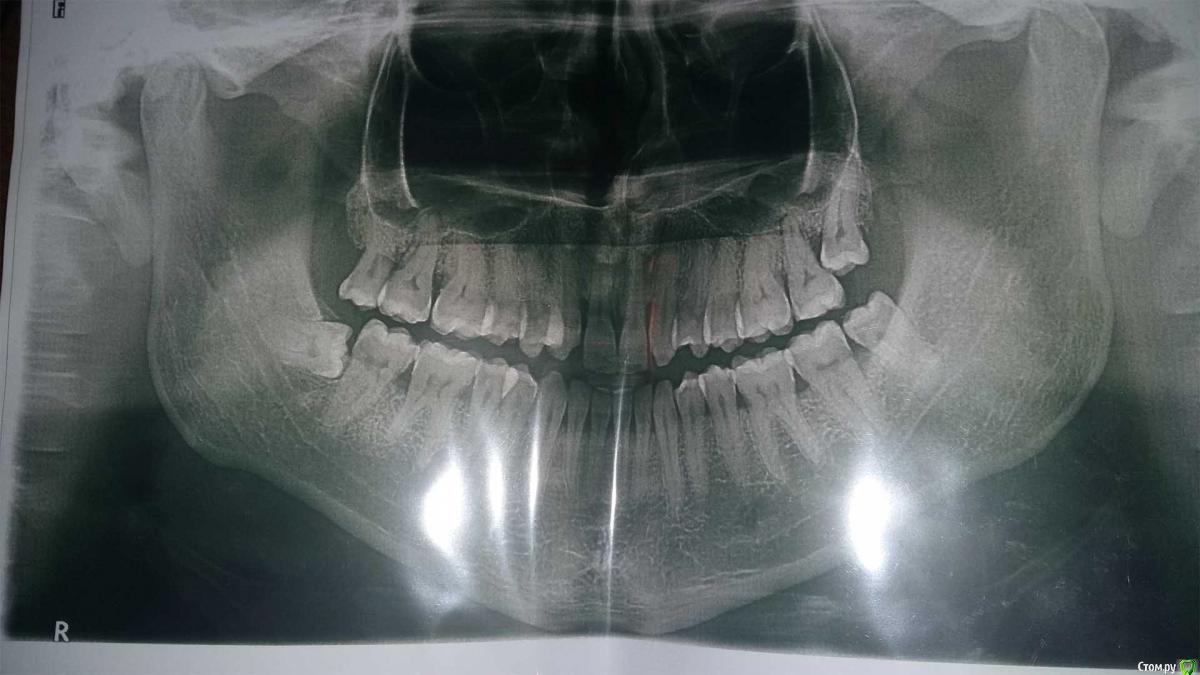

Andrey63 Опубликовано 1 июля, 2019 Поделиться Опубликовано 1 июля, 2019 Добрый вечер уважаемые врачи. Беспокоит состояние прикуса, которое ухудшается с каждым годом, в 18 лет заметил что что-то не так, сейчас уже 28, с прикусом не понятно что. Обращался к трем ортодонтам, один говорит что нужна операция на верхней челюсти, другой говорит что не нужна, третий говорит,что просто зубы на верхней челюсти наклонены во внутрь, поэтому так. В общем я сам запутался. Нижняя челюсть постоянно отвисает в прямом смысле, Я могу путем напряжения каких-то мышц горла задвигать ее назад и таким образом говорить, но если она расслаблена она выдвигается вперед и выговорить ни одну букву я уже не могу. И с 20 лет где-то это вошло в привычку, еще равновесие головы страдает, когда задвигаю челюсть назад. Уже не знаю куда обращаться... Очень хочется говорить свободно, учитывая, что я и так заикаюсь с детства. Ссылка на комментарий